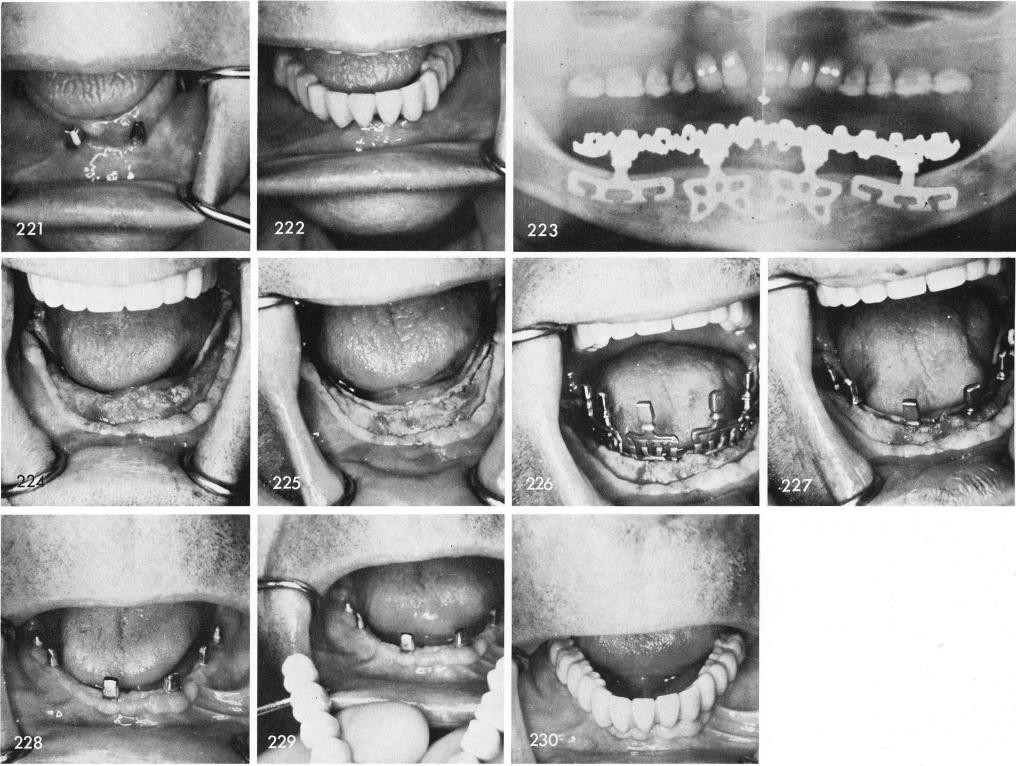

A new prosthesis was processed with the new gold post, fig. 220, that fitted exactly over the remaining portion of the neck and fitted accurately inside the cuspid crown. Fig. 221 shows the new right cuspid post cemented over the broken neck of the blade to help support the new prosthesis, fig. 222. A nine year x-ray shows the case to be working out very well, fig. 223.

When the alveolar bone is dense and thick I often use my newer designed blades which are slightly wider bucco-lingually than the original most widely used titanium blades, fig. 224. The grooves are made in a similar manner but must be made extremely deep and sometimes even slightly widened, fig. 225, to accommodate the broader type blades, figs. 226, 227. The healing is magnificent and the retention of these blades in bone is unsurpassed, fig. 228. A full arch fixed prosthesis is then cemented to place, figs. 229, 230. The post-operative x-ray, fig. 231.